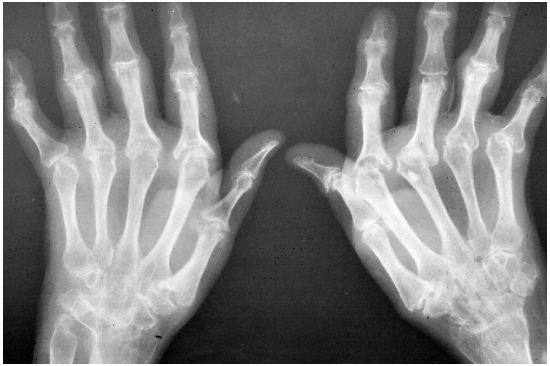

2. 一位43歲女性兩手近端指間關節、兩側的掌指關節(metacarpo-phalangeal joints)及兩側腕關節(wrist joints)疼痛腫脹有9個月之久(如圖 a)。服用消炎止痛劑會有短暫效果,但是上述關節逐漸發生變形 (X-光檢查如圖 b)。ESR>100 mm/1h,CPR 6.36 mg/dl、RF 384 IU/ml,ANA= 1:160 speckled pattern。請問這位患者的首選治療方式為下列何者? (A) Specific COX-2 inhibitor (B) Glucocorticoids (C) Methotrexate (D) Synovectomy (E) Wax thermotherapy